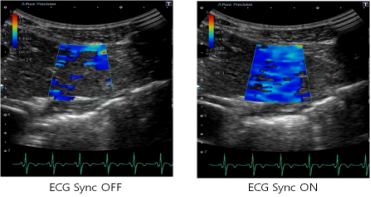

3:SWE的ECG 同步采集:显著减少了伪像,并确保了可以获得更精准的结果,

如下图所示: